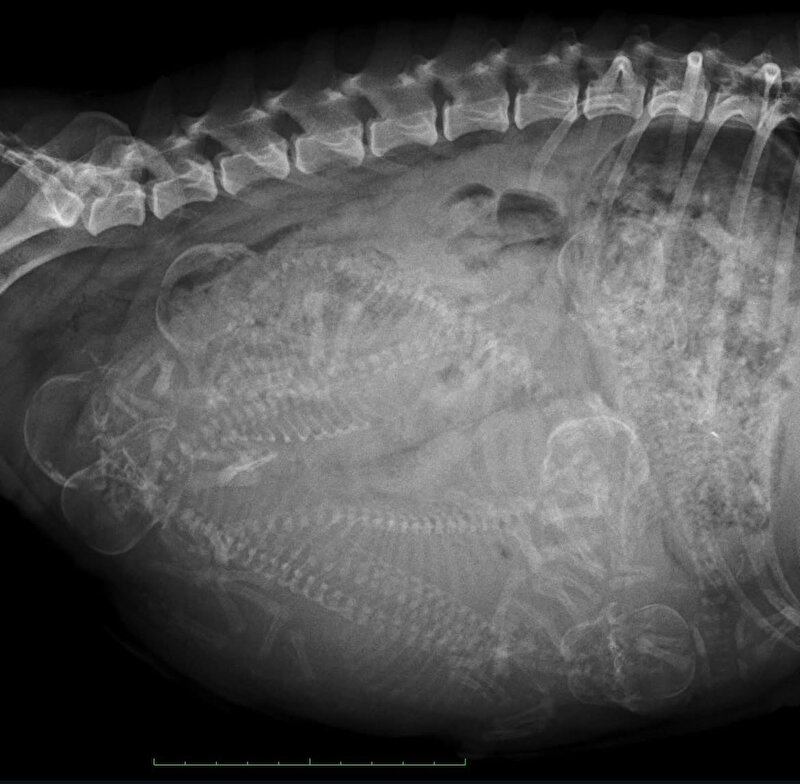

Het kan ook wel. Maar de ervaring is dat je dan gewoon een slecht beeld hebt. Als je wacht tot 55+ dagen zie je het veel duidelijker. En daar doe je t voor..

En altijd van 2 zijkanten foto’s maken. Soms liggen pups wat verstopt en dan zie je ze vanaf de ene kant niet liggen.

En de reden dat ik daar over “zeur” is dat de baarmoeder een vorm van een Y heeft. Dat wil zeggen: 1 baarmoederhoorn linkerzijde hond en 1 rechterzijde. Op de eerste foto lijkt een 5e aanwezig, die op de 2e foto bijna niet meer te zien is. Wat kan betekenen dat er nog steeds een nr 5(of6) aanwezig is, want wat je ook op de foto ziet is een gevulde darm. Ter hoogte van de 3 schedels is het dus te vol van ontlasting om een goed beeld te krijgen.

Maar vooraan vind ik het beeld ook te vaag om duidelijk te zien wat daar zit. Ik zou dus zeker nieuwe foto’s maken en dan van beide kanten.

Het zijn in ieder geval minimaal 4 pups, maar het zou me niets verbazen als er straks nog meer uitkomen.

floorsil schreef:Volg gewoon even mee.maar als ik hoofdjes of ruggengraten tel ik er 6 . Hoe zit dat? Heel veel succes met de laatste loodjes.